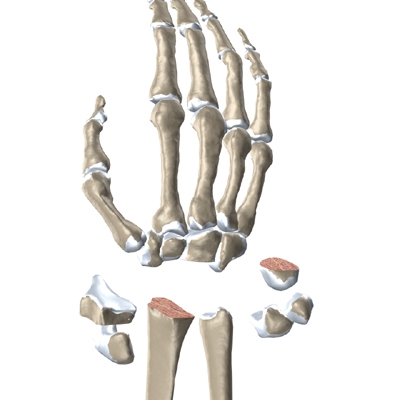

The anatomy of the wrist joint is extremely complex, probably the most complex of all the joints in the body. The wrist joint is actually made up of many joints and many bones. These joints and bones let us use our hands in many ways. The wrist must be extremely mobile to give our hands a full range of motion. At the same time, the wrist must provide the strength for heavy gripping.

The wrist is made up of eight separate small bones, called the carpal bones. The carpal bones connect the two bones of the forearm, the radius and the ulna, to the bones of the hand. The metacarpal bones are the long bones that lie mostly underneath the palm. The metacarpals are in turn attached to the phalanges (the bones in the fingers and thumb).

One reason that the wrist is so complex is that every small bone forms a joint with the bone next to it. This means many small joints make up the wrist joint. Ligaments connect all the small bones to each other, and to the radius, ulna, and metacarpal bones.

The surgeon needs to make room for the artificial joint. To do this, most of the first row of:

Carpal Bones are Removed

from the wrist. The end of the radius is also shaped to fit the prosthesis.